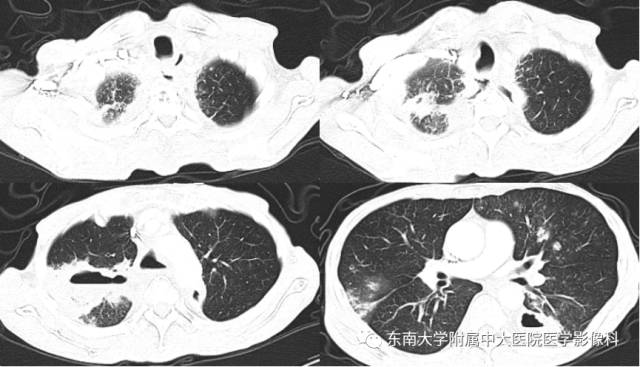

• 【病例】肺泡蛋白沉积症1例CT影像表现

【病例】肺泡蛋白沉积症1例CT影像表现